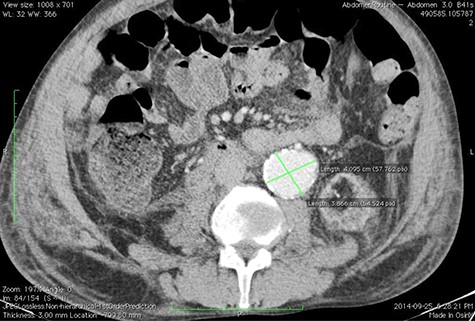

Given the rapid decompensation in the patient, a simultaneous liver-kidney transplant was proposed, but because the accepted diameter of aneurysm for surgical management is 5.5 cm and higher [1], it was decided to closely follow-up with the patient post-transplantation. The liver was transplanted using the piggy-back technique, inferior vena cava was anastomosed side-to-side, and portal veins and hepatic arteries were anastomosed end-to-end. The donor kidney was placed in the right iliac fossa with anastomosis of the right internal iliac artery and vein in an end-to-end fashion. The patient then had an uncomplicated post-operation course and was discharged with an immunosuppressive regimen. One month later, the patient came to the emergency room with severe abdominal pain. To rule out possible aneurysm rupture, an emergent CT scan with contrast was performed; however, the findings were compatible with an infrarenal aortic aneurysm with eccentric mural thrombosis. In addition, the aneurysm had grown in size and had a diameter of 5.2*6.5 (Fig. 2).